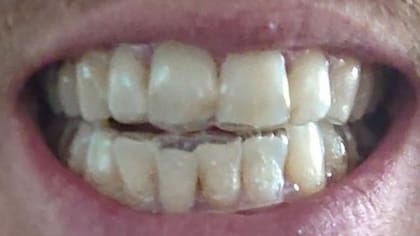

Pero después de cumplir los seis meses de tratamiento, Jamie publicó esto en Reddit. “Uno de mis dientes frontales se movió mi esmalte se siente raro, como si los alineadores hubieran removido parte de él. Los alineadores hicieron que mi encía se reduzca lo que es una agonía”.

La odontóloga Victoria Sampson afirma que los usuarios pueden subestimar la fuerza que los alineadores ejercen sobre los dientes. Si no se detectan caries o enfermedades de las encías en una revisión física, se corre el riesgo de perder algunos dientes.

Dice que trataron a alguien que perdió un diente frontal después de usar los alineadores porque le movieron los dientes demasiado deprisa, desviando su mordida.